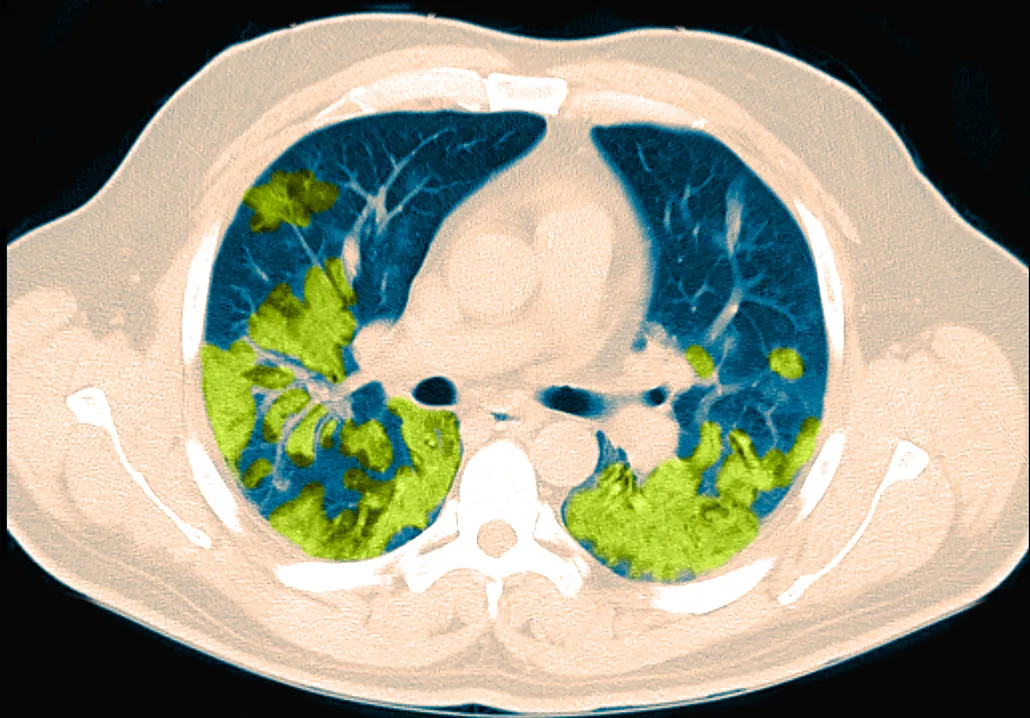

There’s no denying that, when warranted, CT scans are a crucial, lifesaving part of the medical toolkit. Recently, the scans have been in the spotlight for revealing damage done to the lungs by COVID-19 (SN: 4/27/20). The technology seems poised to remain a mainstay of medicine and science in future decades, continuing to scan its way into our hearts, lungs, brains and everywhere else.